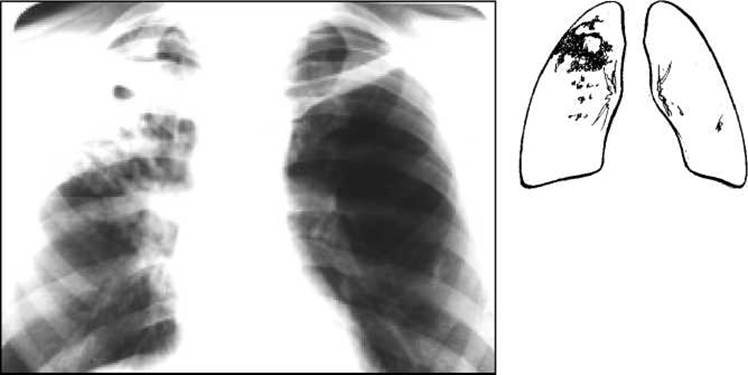

При рентгенологічному дослідженні в легенях знаходять неоднорідну тінь, частіше у верхній частці легень (рис. 18) або в прикореневій ділянці, що відповідає верхівці нижньої частки. Коли інфільтрат розпадається, в його центральній ділянці видно просвітлення неправильної або округлої форми (каверну). Типовими для туберкульозного інфільтрату є дрібні вогнищеві тіні навколо нього або в іншій легені (вогнища бронхогенного обсіювання). В таких випадках встановлюють діагноз інфільтративного туберкульозу легень у фазі розпаду і обсіювання.

Рис. 18. Рентгенограма органів грудної клітки. Справа під ключицею неоднорідний інфільтрат з порожниною розпаду. Нижче - вогнища бронхогенної дисемінації.